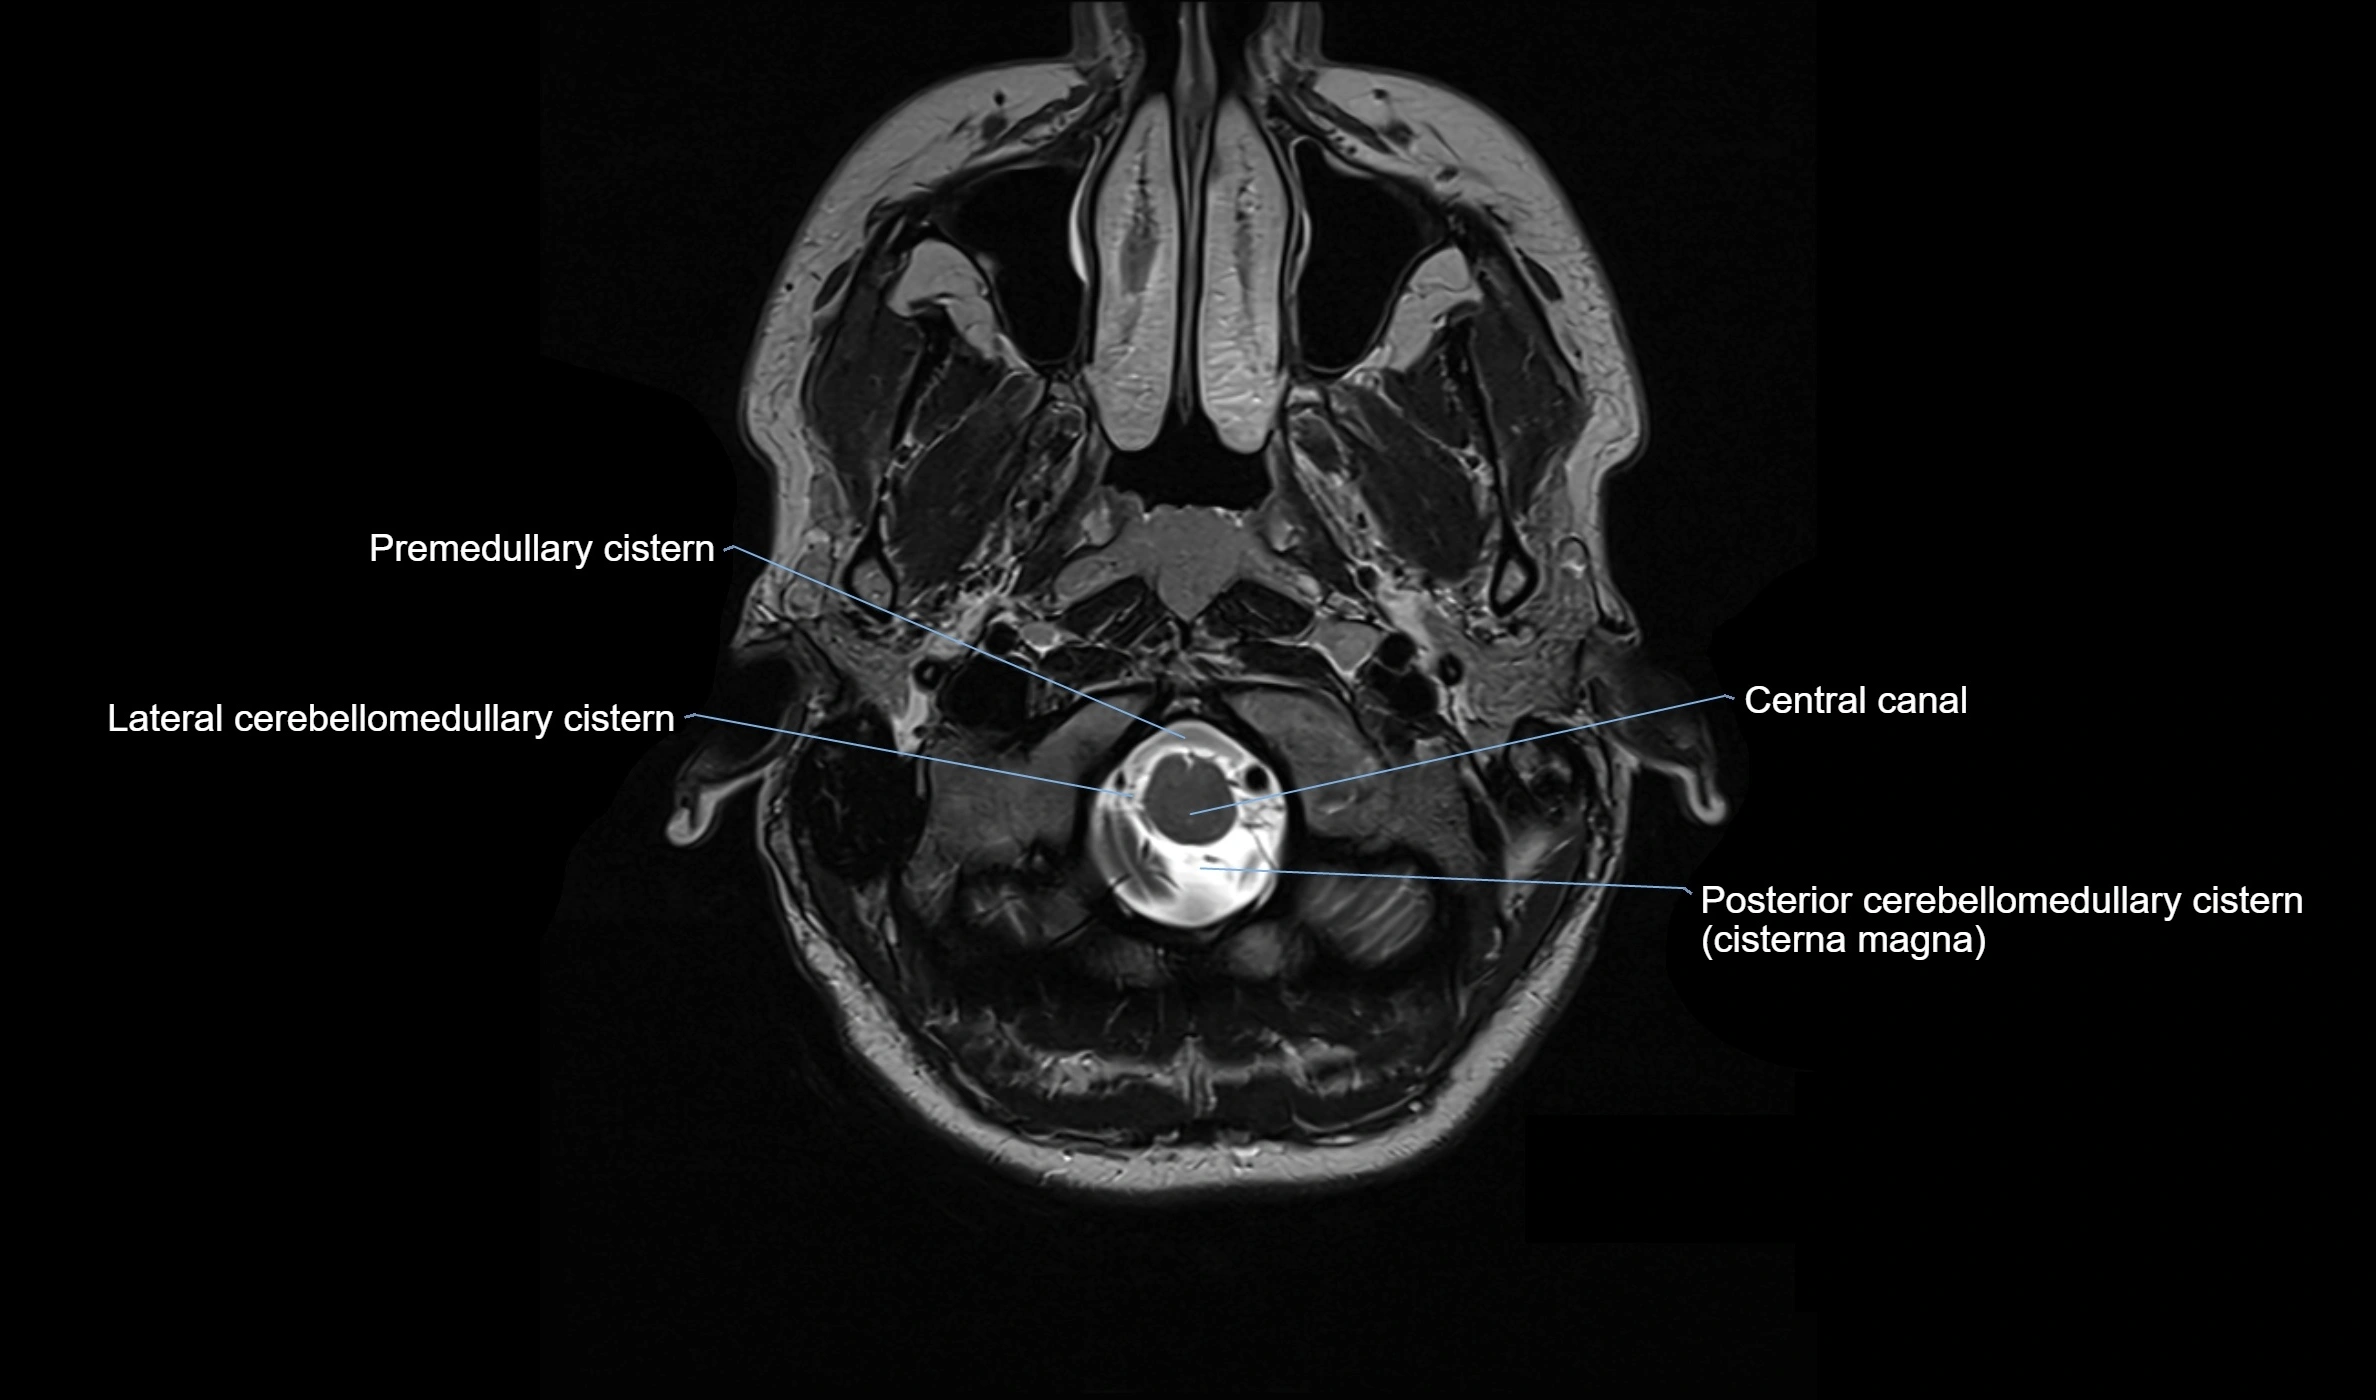

MRI images

image